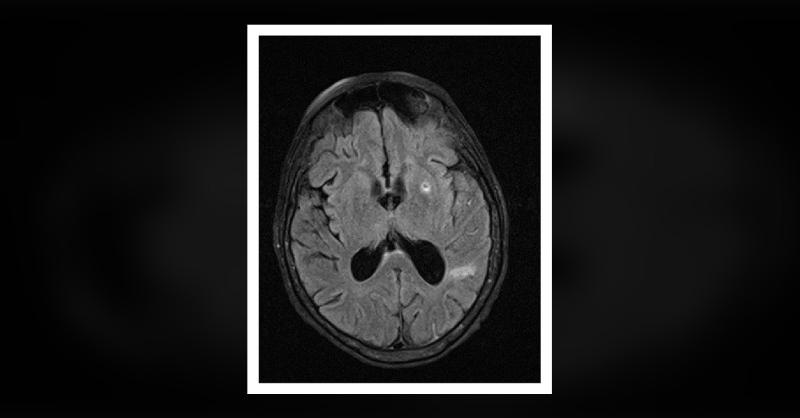

A 65-year-old Caucasian woman with a past medical history notable for hypertension, hyperlipidemia, hypertrophic cardiomyopathy with left ventricular outflow tract obstruction, and mitral regurgitation presented with confusion and fevers. She had no prior surgeries but underwent routine dental cleaning four months before her presentation. Despite a